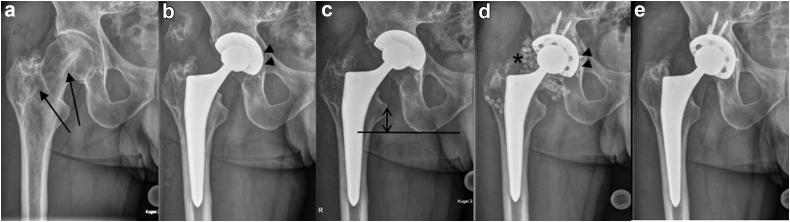

Periprosthetic joint infection remains a major complication in arthroplasty. We present the first description of a case of periprosthetic joint infection with , microorganism that is mostly found on the skin of the upper body and might cause particular challenges as it is difficult to culture and specify. Furthermore, a thorough microbiologic workup may indicate the source of infection. In this case, it is possible that perspiration from the surgeon was the source of intraoperative contamination. Intraoperative contamination through perspiration may be important and should be avoided by all means.

人工关节周围感染仍然是关节置换术中的主要并发症。我们首次描述了一例人工关节周围感染病例,感染的微生物主要存在于上半身皮肤,因其难以培养和鉴定,可能会带来特殊挑战。此外,全面的微生物学检查可能会揭示感染源。在本病例中,外科医生的汗液有可能是术中污染的来源。通过汗液造成的术中污染可能很重要,应想尽办法避免。